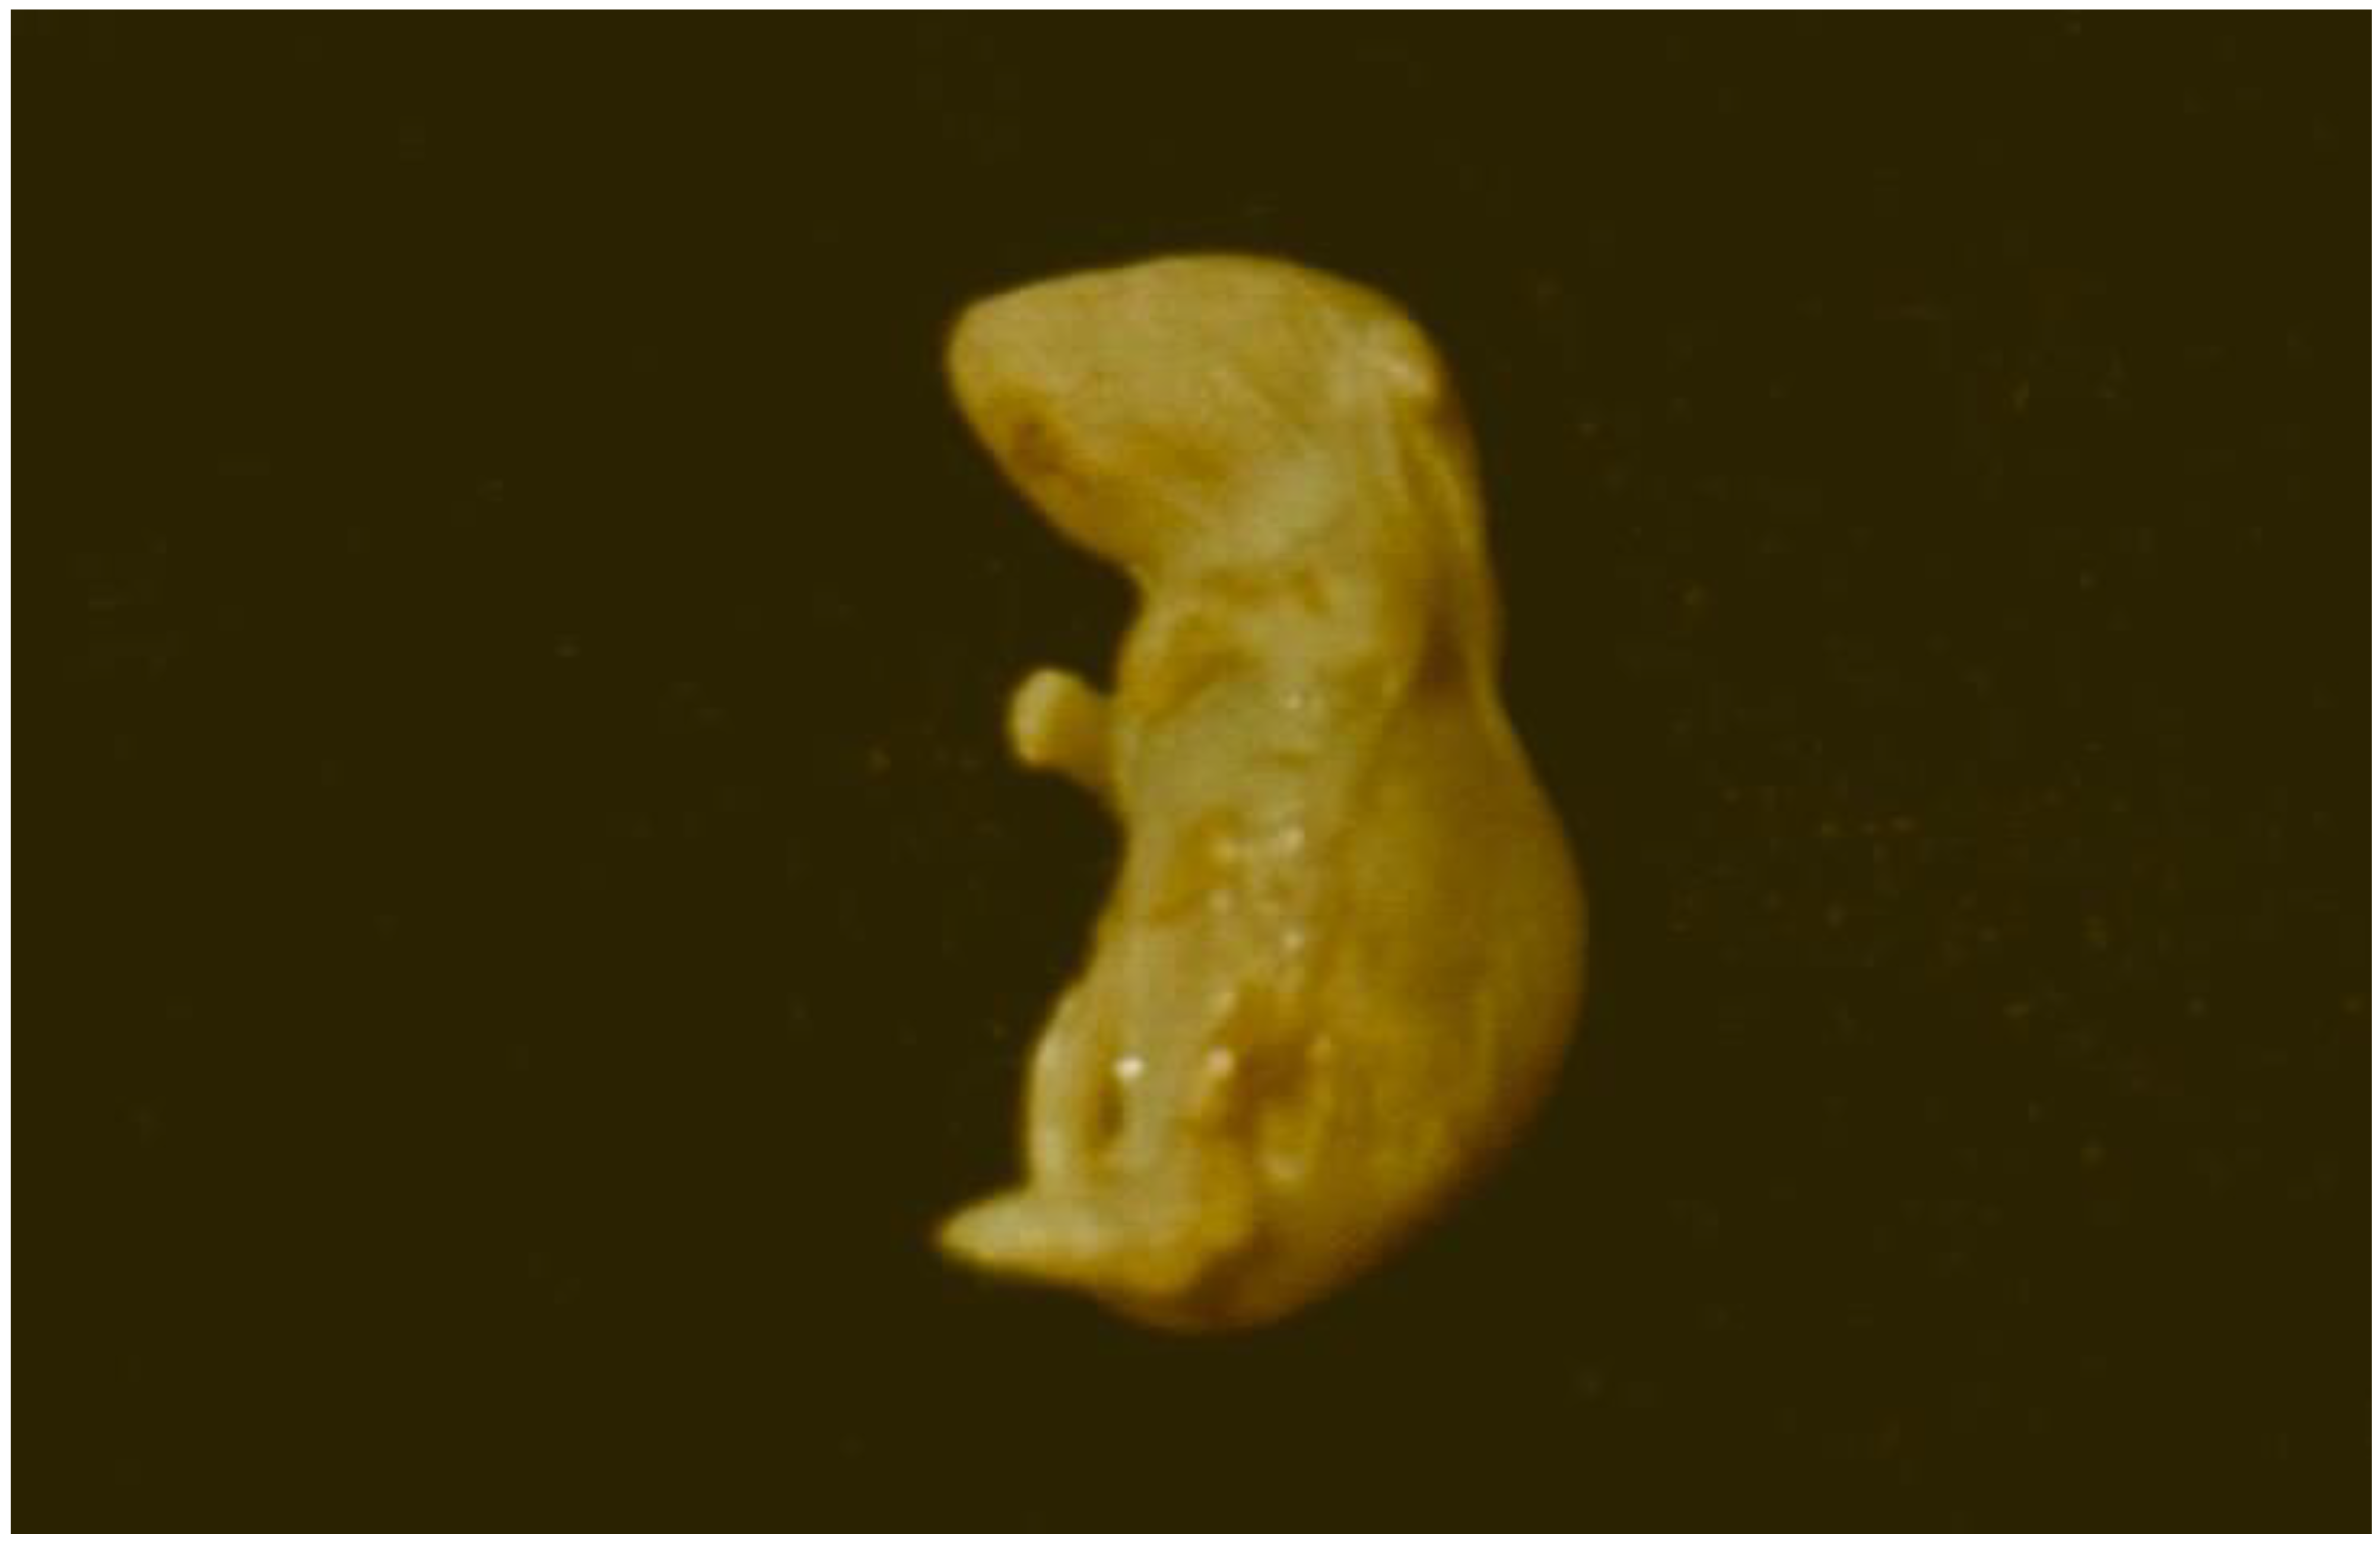

- Stoev, S.D. Studies on teratogenic effect of ochratoxin A given via mouldy diet in mice in various sensitive periods of the pregnancy and the putative protection of phenylalanine. Toxicon 2022, 210, 32–38. [Google Scholar] [CrossRef] [PubMed]